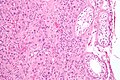

| LM | cytoplasmic vacuolization, cytoplasm -- clear to eosinophilic, +/-Reinke crystals (cylindrical crystalloid -- eosinophilic cytoplasmic bodies), +/-nucleoli common, round nuclei |

- Vacuolization (cytoplasm) - key feature.

- Cytoplasm - clear to eosinophilic - important.

- Usually eosinophilic.

- Reinke crystals - classic finding, usually not present.

- Cylindrical crystalloid eosinophilic cytoplasmic bodies.

- Nucleoli common.

- Round nuclei.